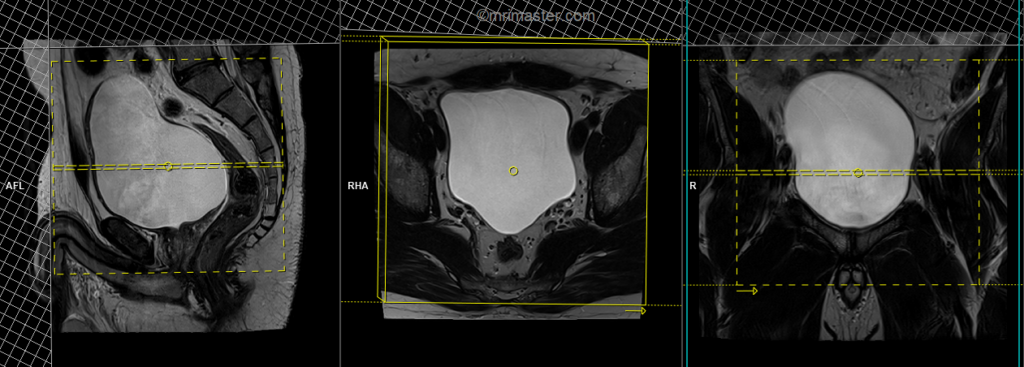

T2 tse axial 3mm SFOV

Plan the axial slices on the sagittal plane and angle the positioning block horizontally across the urinary bladder. Check the positioning block in the other two planes. An appropriate angle must be given in the coronal plane, horizontally across the urinary bladder. Slices should be sufficient to cover the urinary bladder from L1 down to two slices below the symphysis pubis. To reduce artifacts from breathing and peristalsis, consider using a saturation band above and in front of the axial block.

Parameters

TR 4000-6000 | TE 100-120 | SLICE 3 MM | FLIP 130-150 | PHASE R>L | MATRIX 320X320 | FOV 200-250 | GAP 10% | NEX(AVRAGE) 2 |